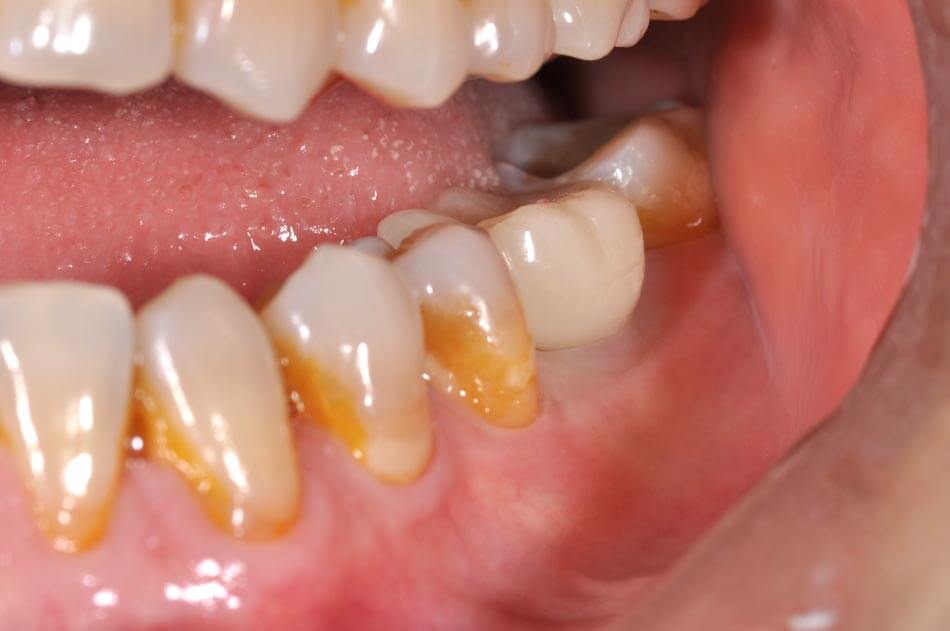

植牙前

植牙後

更多植牙案例